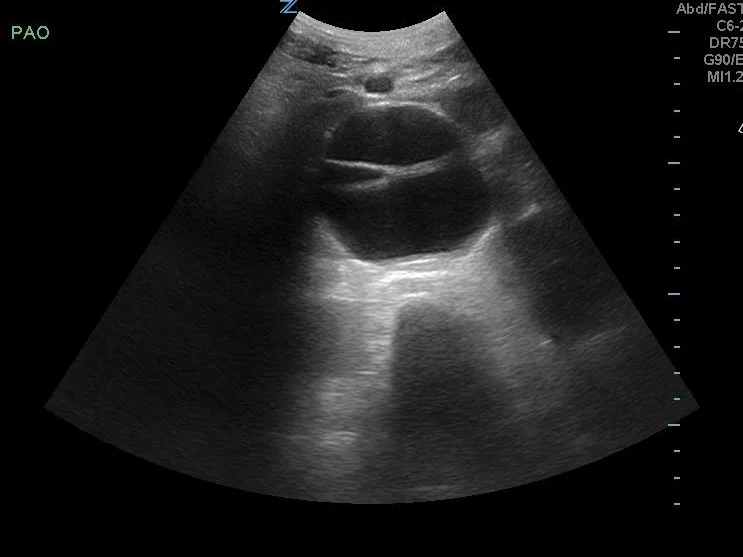

AAA

Transverse view